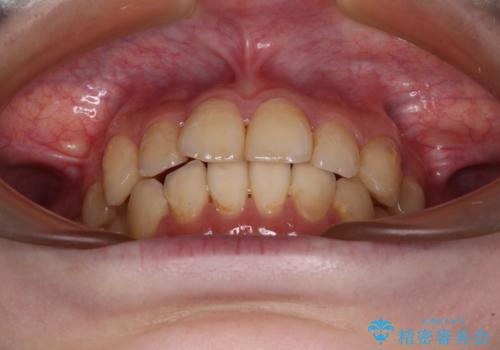

デコボコ歯列をきれいに インビザラインによる矯正治療

- 上下歯列全体のデコボコを気にして来院された患者様です。

主に下顎歯列全体の後方移動とIPR(歯と歯の間を削る)によってデコボコが解消するように設計し、インビザラインにより治療を行うこととしました。